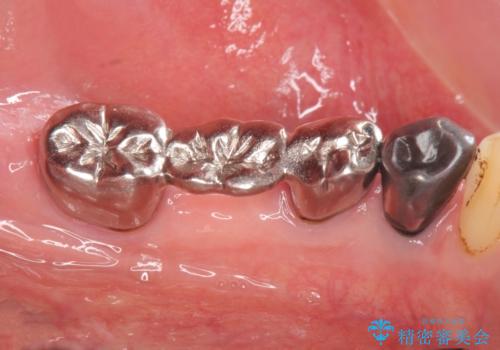

- 古くなり黒ずんできたブリッジのやりかえを希望され来院されました。

老朽化した銀パラジウム合金のブリッジを除去し、ジルコニア製のブリッジでやりかえを計画します。